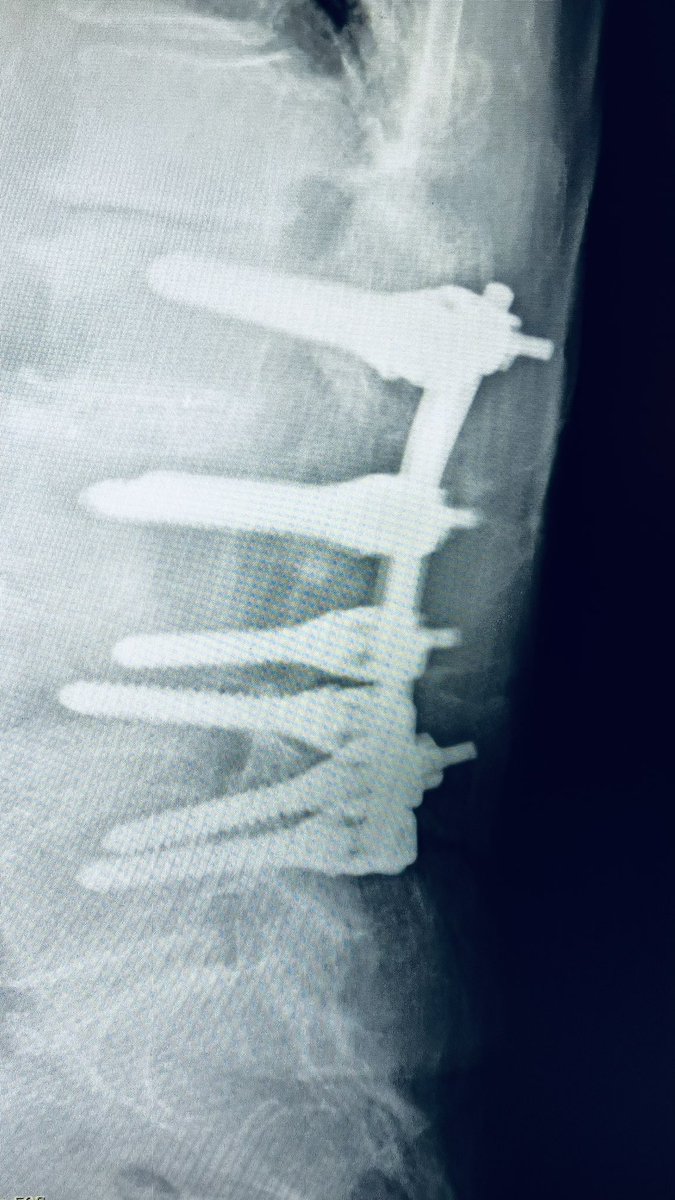

@atmghn There is a Facebook group dedicated to the identification of spinal implants. facebook.com/groups/3604528…